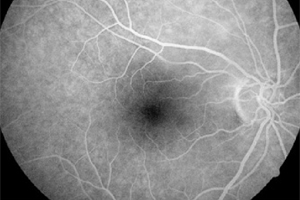

Unter einer Angiografie versteht man eine Gefäßdarstellung, mit der die Durchblutungssituation der Netzhaut beurteilt werden kann. Dies ist unter anderem wichtig bei altersabhängiger Makuladegeneration, diabetischen Netzhautveränderungen oder Durchblutungsstörungen z.B. aufgrund einer Thrombose, oder auch Tumoren.

Um die Gefäßdarstellung durchführen zu können, wird ein gelber Farbstoff in die Armvene injiziert. Anschließend werden mit einer speziellen Fotokamera Bilder von den Blutgefäßen am Augenhintergrund angefertigt. Aufgrund des in die Blutbahn gelangten Farbstoffes können die Gefäße, Gefäßverschlüsse, Gefäßneubildungen (Neovaskularisationen) und auch durchlässige Bereiche (Leckagen) gut dargestellt werden. Die fotografischen Aufnahmen ermöglichen eine genaue Darstellung der abnormen Blutgefäße oder der Größe und Lage des Gefäßverschlusses.

Die Fluoreszeinangiographie wird ambulant im Rahmen einer speziellen Sprechstunde durchgeführt.

Normalbefund